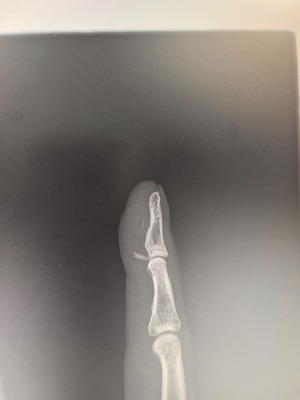

そして指に違和感あったのでレントゲン撮影したら右手指先第一関節部に異物・・・

取れんのか?担当医は手術しましょうと・・・

こんなの自分でほじくってピンセットで抜けるだろうと思ったら甘かった

手術は結構先になるとのことで紹介状書いてもらって他の町医者行くもできない・・・

かなり難しいようで結局病院差し戻しで日程調整して執刀されました

無事とりぞけまして私も大喜び、謝意述べたら執刀医と担当医からもこちらに感謝の言葉・・・なぜ?

良いサンプルなったようです

私の指にいつからか入ってたこの異物はなんと鯛の鰭でした

おそらくタイ王国滞在中だと思います、刺身食いたいと思って自宅でやった時だな

日本帰ってきてから腫れて痺れ、疼痛の違和感

取れてよかった

失敗して入りっぱなしの方もいらしゃるそうです、結構難しいようですね、私はかなりの幸運らしく、私の感覚的な位置と若い執刀医の感で一発完了だったそうです

見つからない時は2箇所3箇所切るので後々大変、しかも見つかればいいけど・・・だそうです

執刀中は見てましたがかなりの出血でした、エグかった

縫合して1週間後抜糸で今はほぼ完治です、一安心です

事前に手術費用を聞いていたのですが結構かかるなーでした

生命保険通そうと連絡しましたら指は適用外、手のひら甲から、入院するなら入院費用は適用でした・・・無念

日帰り手術でしたから当日1時間前に受付、約40分の手術時間

移動(かなり不便な場所にある)、拘束時間含め2時間ほど

結局かかった費用が・・・この金額でいいの?と思いました、なぜ私に忖度?

驚くほど安かった、びっくりです

除去物はお守り代わりに持ち歩き